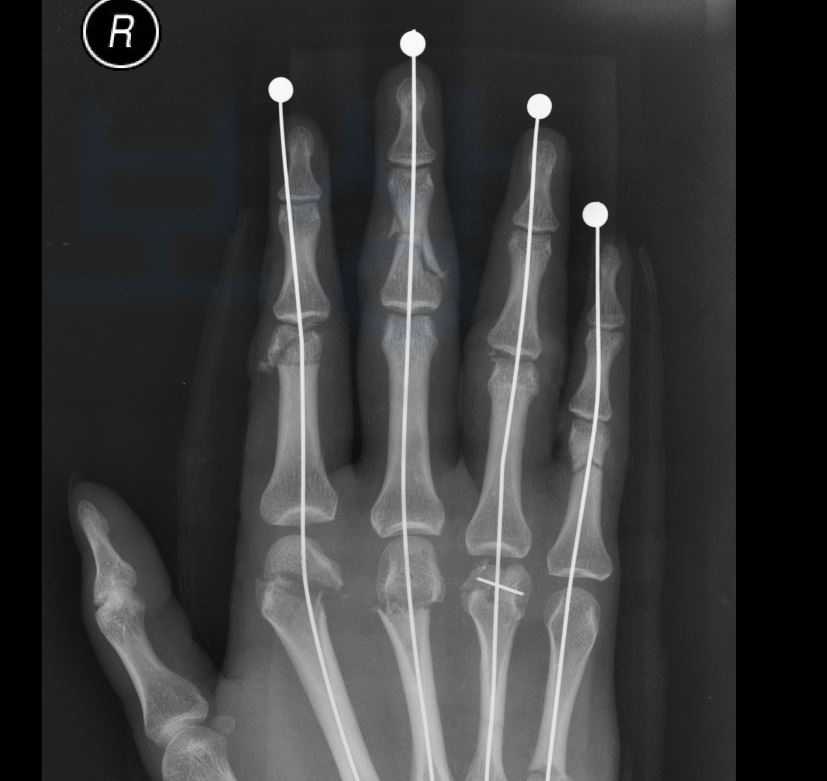

의뢰인은 한 제조공장에서 일하시던 중 제품불량을 발견해 기계에서 뽑아내려다 손가락이 절단되는.. 사고를 당하셨습니다. 위 영상 사진을 보시면 당시 사고가 얼마나 심각했는지 짐작하실 수 있습니다.

의뢰인의 경우 절단된 손가락을 모두 접합 및 금속 고정을 하였지만 손가락의 힘줄과 신경손상이 동반되어 향후 기능장해의 잔존이 예상되었습니다. 산재 장해급여 청구는 산재 요양 및 치료가 종료되고 치료의 효과를 더 이상 기대할 수 없거나 그 증상이 고정되었을 때 평가합니다.